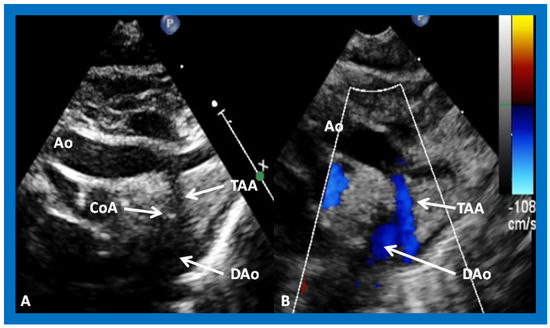

In Type II patients, the VSD may be small, causing obstruction to blood flow to the systemic circuit, and, therefore, the size of the VSD should be ascertained by 2D (Figure 11 and Figure 12), color Doppler (Figure 12), pulsed (Figure 15) and CW Doppler, as necessary. In these Type II patients, a high VSD velocity is indicative of subaortic obstruction. Interrogation of the LV outflow and PA region may reveal pulmonary or subpulmonary stenosis; the higher the velocity, the more severe is the obstruction. Studies from the suprasternal notch may show aortic coarctation (Figure 16), which is common in patients with Type II anatomy.

Figure 16. Selected video frames from suprasternal notch views of the aortic (Ao) arch in 2D (A) and color flow (B) images of a neonate with tricuspid atresia and transposition of the great arteries, demonstrating coarctation of the aorta (CoA) and a hypoplastic transverse aortic arch (TAA) and isthmus. The association of CoA with tricuspid atresia, plus transposition of the great arteries, is well known. DAo, descending aorta. Reproduced from Reference [29].